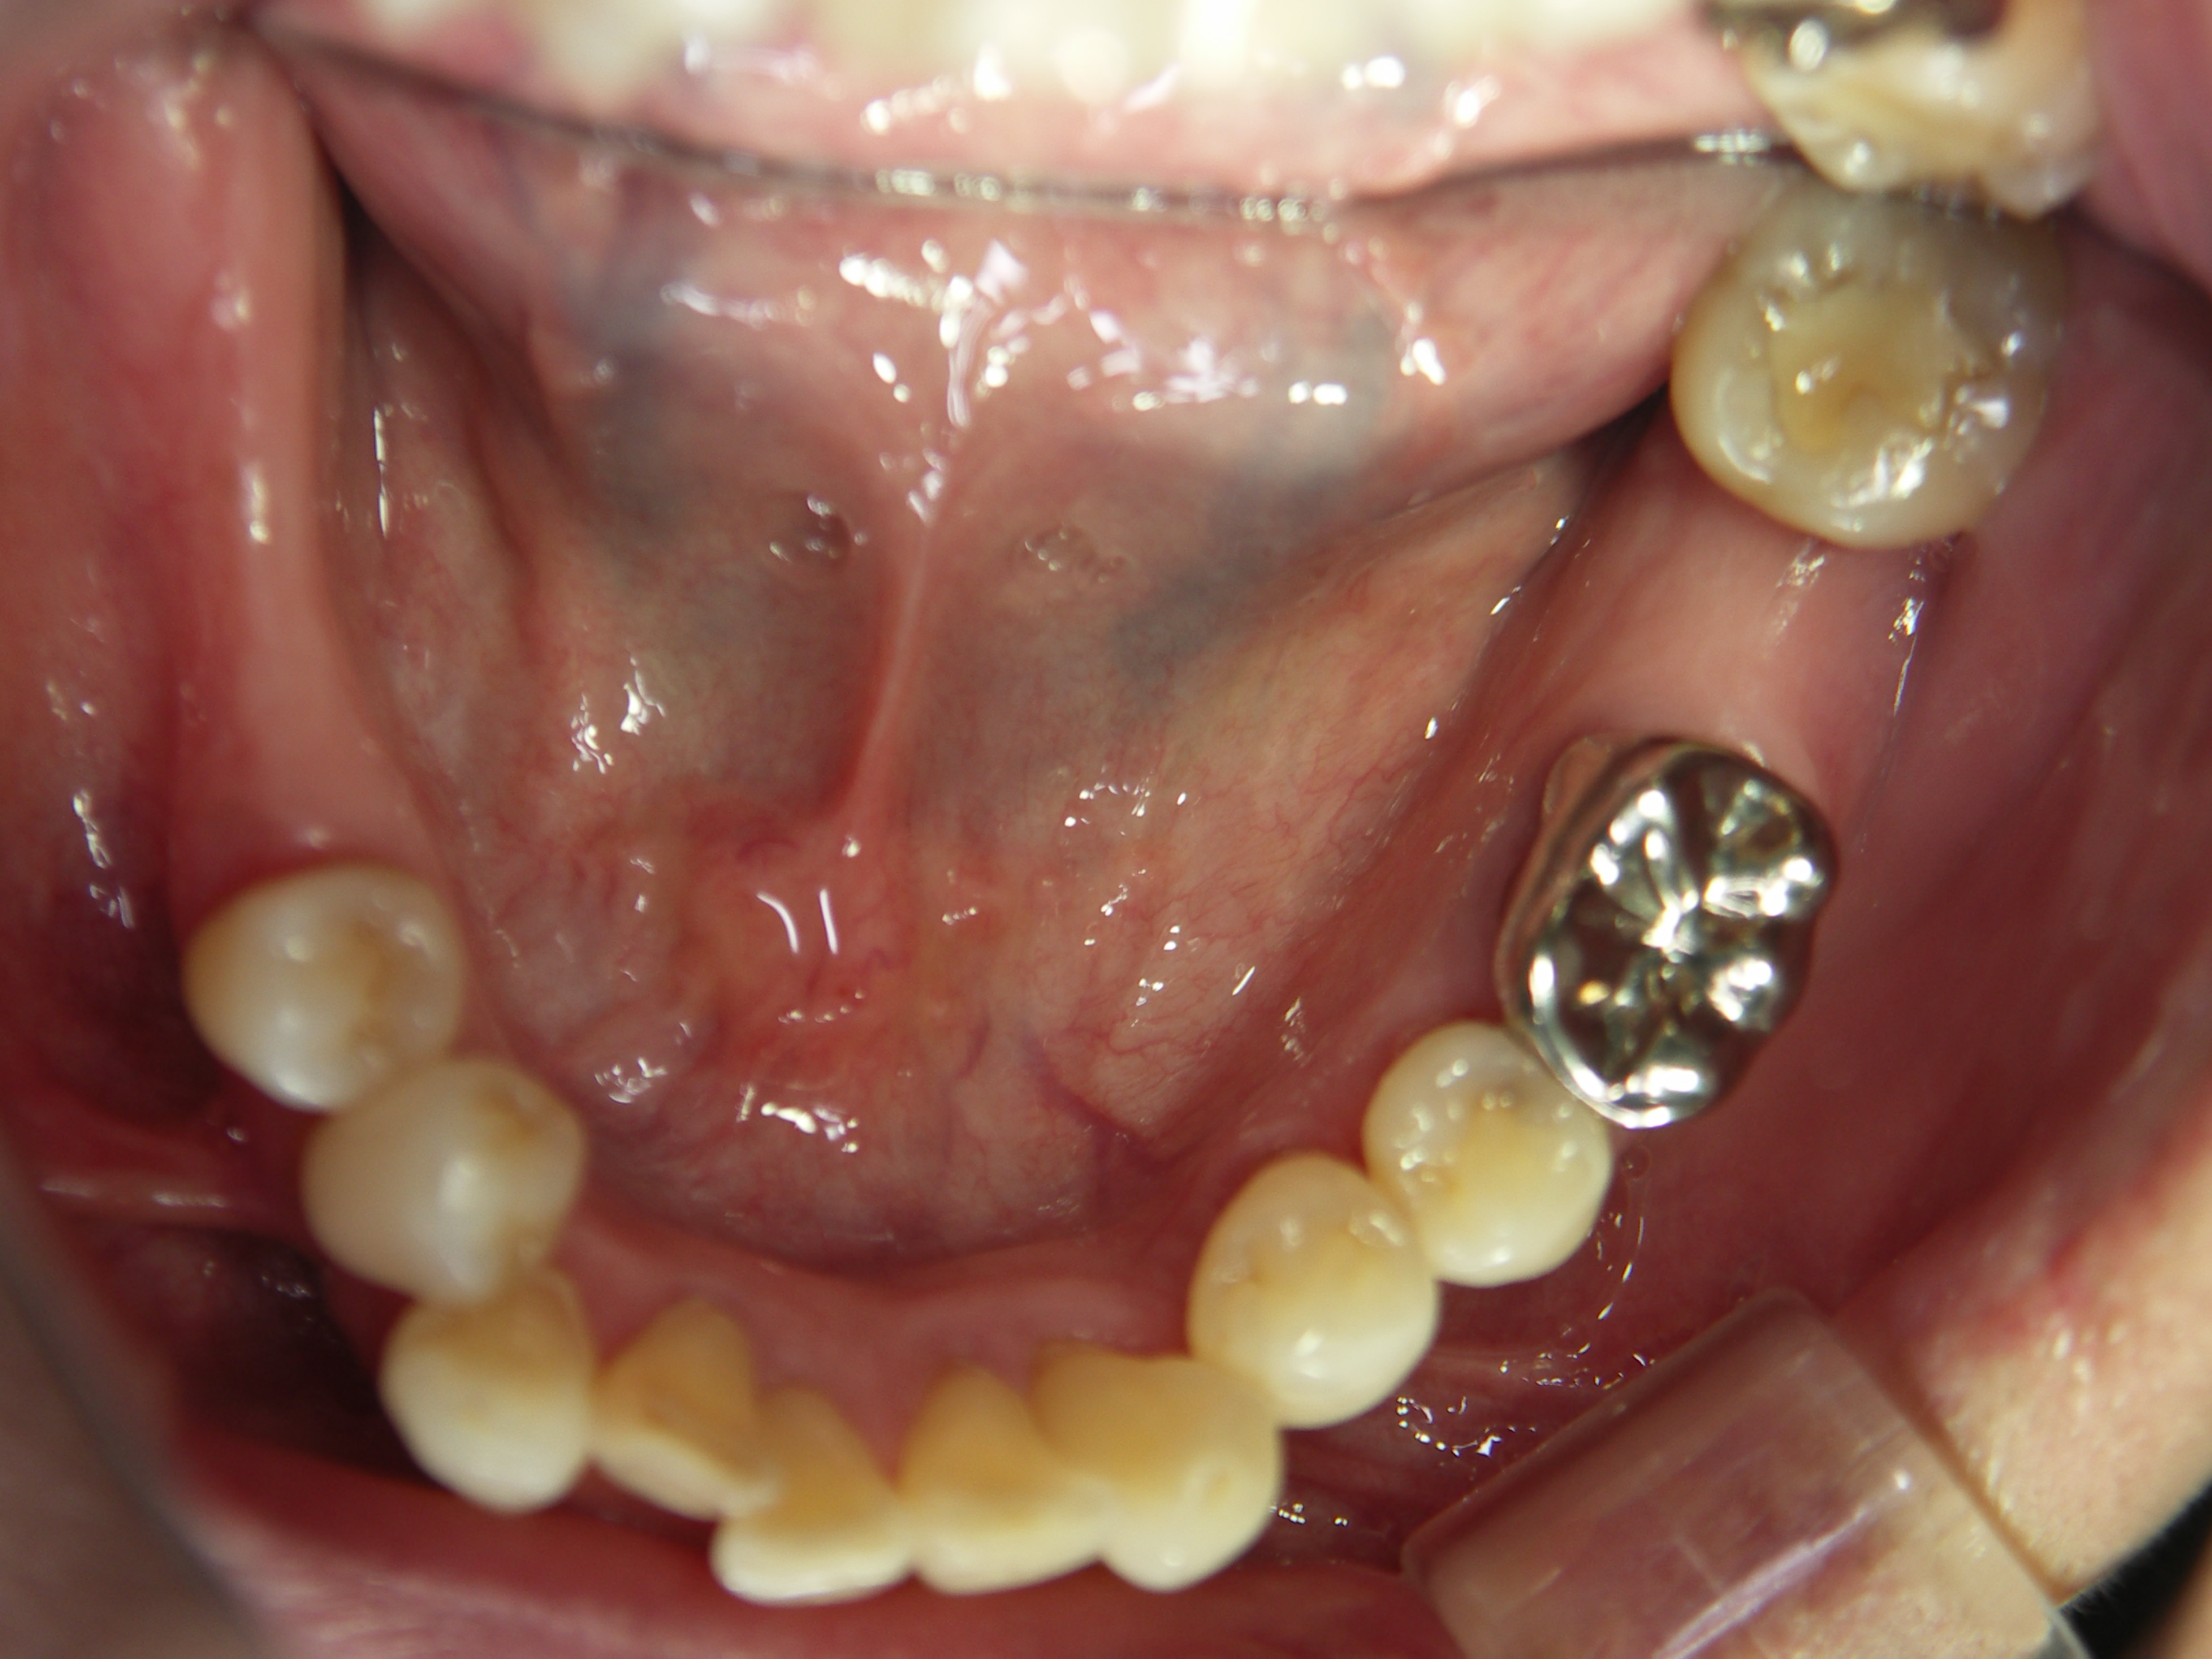

最終補綴物装着時口腔内写真 DT:小見川 純

患者様も大変満足されました

最終補綴物装着時X線写真